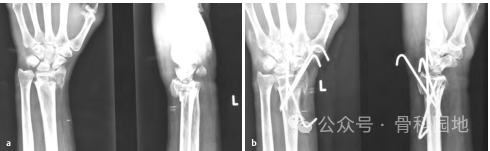

首先进行骨折闭合复位,牵引时须缓慢而持续,通过掌屈和尺偏来矫正背侧和桡侧移位。复位后,将手放在卷起的布单上,保持掌屈和尺偏(下图a,b),并用至少三根经皮克氏针固定。

9、桡骨茎突骨折伴背侧移位,复位后,用两根桡骨茎突克氏针固定:一根位于背侧,另一根位于掌侧至茎突尖端。(下图a、b)